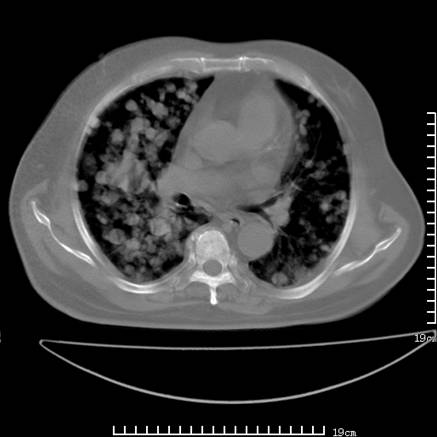

张男,75岁,干咳半年余,小便不利二年,b超检查前列腺增大,未见明显肿块;前列腺癌血生化检查多项指标明显增高。

双肺内多发转移瘤,纵膈淋巴结转移。来源前列腺?建议盆腔mri进一步检查。

双肺转移满了。

两肺广泛转移瘤。